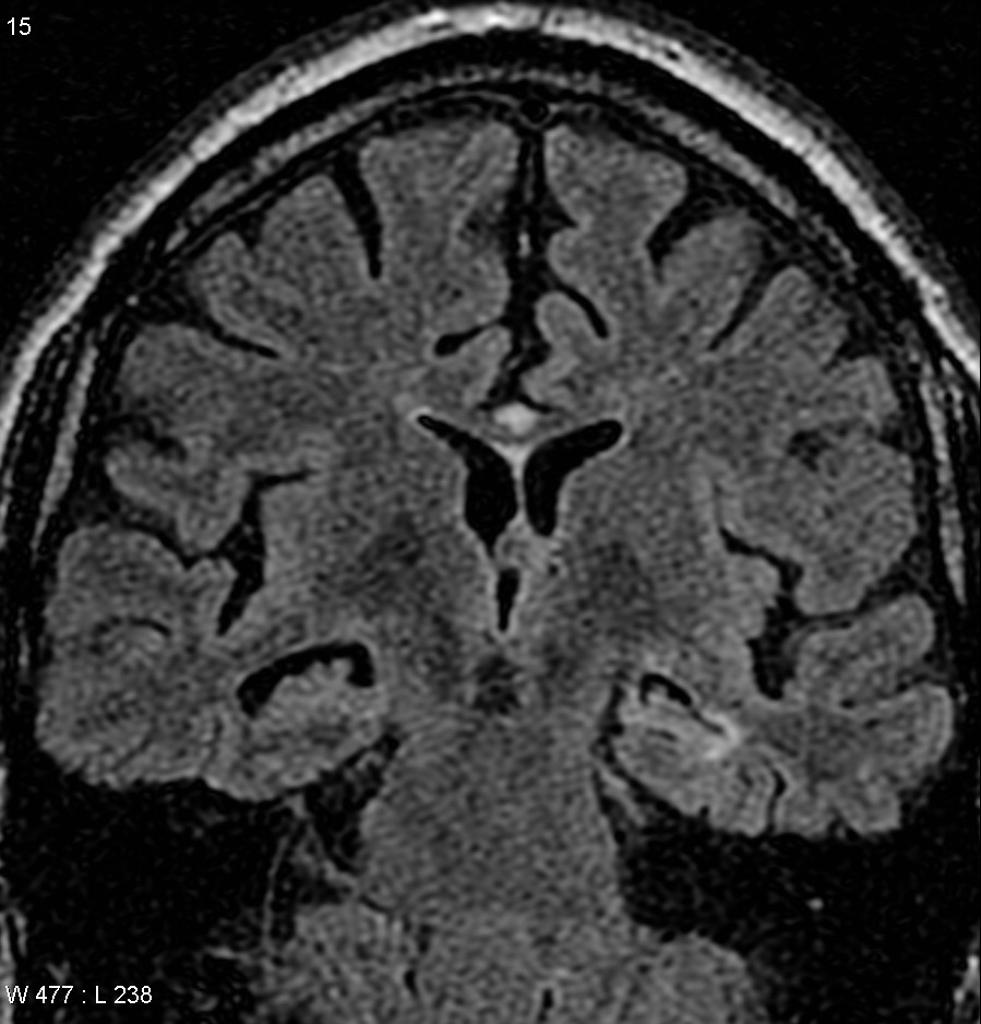

Atrophie hippocampique (Scheltens) Chargement JPEG DICOM Anamnèse Evaluation de l’atrophie hippocampique (atrophie temporale médiale) dans la maladie d’Alzheimer sur une IRM coronale T1 Score Largeur de la fissure choroïdienne Largeur de la corne temporale Hauteur de la formation hippocampique 0 N N N 1. Ainsi la sclérose hippocampique qui était une donnée postopératoire de bon pronostic est devenue, grace à l’IRM, une donnée préopératoire de grande valeur En effet ce type d’anomalie est caractéristique du foyer épileptique luimême. Résumé d’article Résumé d’article Bref résumé d'une publication récente, réalisé par des rédacteurs scientifiques L’imagerie révèle un profil d’atrophie distinct de la sclérose de l’hippocampe liée au vieillissement.

Sclérose hippocampique associée à l’épilepsie La sclérose hippocampique associée à l’épilepsie (SHAE) est la cause la plus fréquente d’épilepsie pharmacorésistante 2 , 3 La physiopathologie en reste mal comprise et repose probablement sur des mécanismes différents selon les patients 4. L´épilepsie temporale mésiale avec sclérose hippocampique pharmacorésistante est un traitement de référence depuis plus de 30 ans Cette efficacité a été confirmée récemment dans deux études contrôlées nordaméricaines Néanmoins, différentes approches chirurgicales ont été décrites. Sclérose hippocampique IRM cérébrale (coupe T2 sur les hippocampes) hypersignal T2, perte des digitations hippocampiques et diminution de la hauteur de l’hippocampe droit Hippocampe gauche normal.

Mieux visible en 1,5 Tesla, à opérer;. Cependant, l'AK est devenu plus populaire lorsque ) ont validé que le modèle induit par injection intrahippocampique d'AK conduisait à une lésion de sclérose hippocampique très localisée. Les critères de diagnostic de sclérose hippocampique en FSE T2 et en FLAIR étaient une diminution de la taille de l'hippocampe et un hypersignal hippocampique 8, 10 Les IRM ont été revues indépendamment par deux observateurs.

Sclérose hippocampique Sclérose de la corne d’Ammon = sclérose temporale mésiale;. Il est cependant indispensable de s'assurer de la localisation du point de départ de la crise bonne corrélation entre mises, EEG et. Sclérose hippocampique = atrophie hypersignal T2/FLAIR « Human hippocampus » Duvernoy.